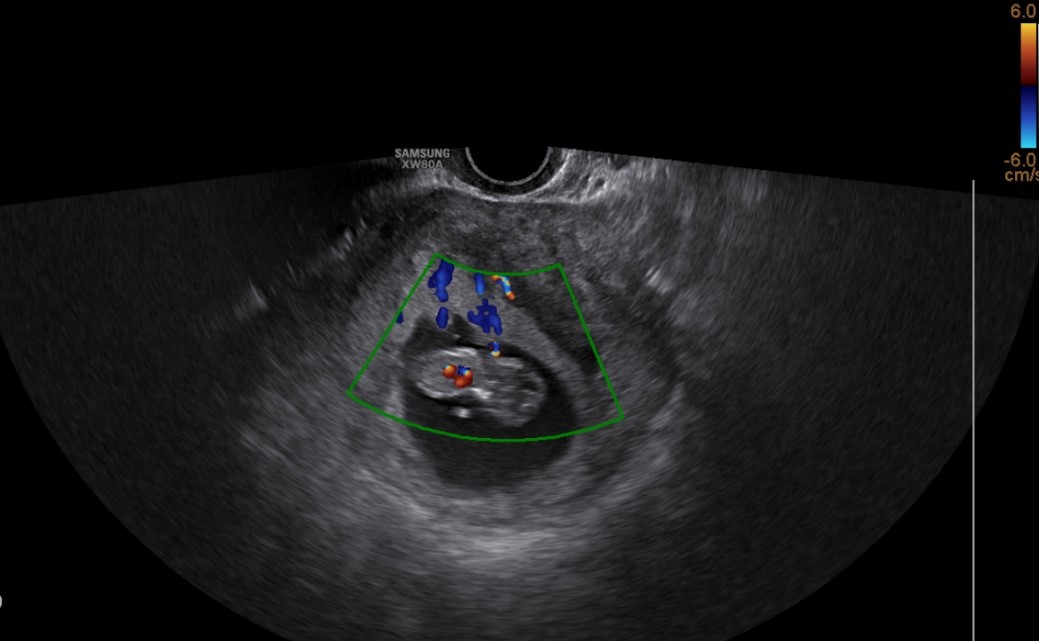

试管婴儿的B超图片

近日,苏州大学附属第四医院生殖医学中心内,一对受“非梗阻性无精子症”困扰多年的高龄夫妻,通过“显微镜下睾丸切开取精术—精子冷冻保存—试管婴儿”一体化治疗,成功妊娠,现已至产科建卡。这一成果标志着我院生殖中心在男性不育诊疗领域实现了重要突破,建立了成熟、稳定、体系完备的各类睾丸取精技术与精子(精液、睾丸组织、单精子)冷冻平台,为更多遭遇类似情况家庭点亮了生命之光。